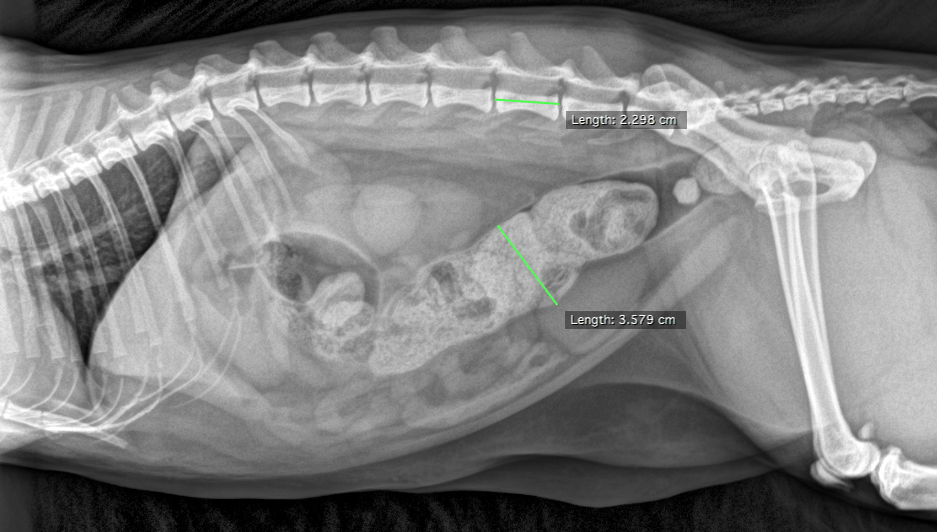

This 5 year old MN DLH cat has a history or constipation of 6-12 months duration and presented today for constipation and lethargy.

Physical exam: tense non painful abdomen, large diameter of hard fecal material in colon